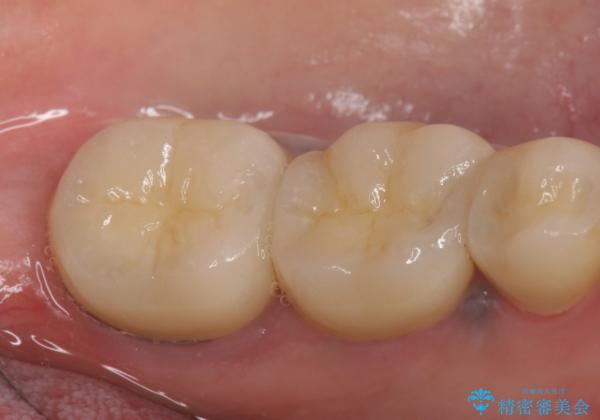

症状の消失を確認後、オールセラミッククラウンによる補綴を行いました。

今回用いたオールセラミッククラウンは、ジルコニアフレームという白い素材の上にセラミックを盛っているため審美性が非常に高いのが特徴です。

またジルコニアは人工ダイヤモンドの材料にも使われているほど高い強度を持っており、そのためオールセラミッククラウンは審美性だけでなく、奥歯やブリッジの補綴も可能とするクラウンです。